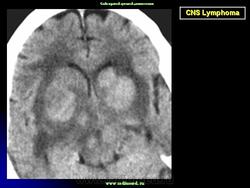

Диагноз подозревается на основе изображений КТ и МРТ.

TRM Difusión (MRI DWI.Exponential Apparent Diffusion Coefficient)